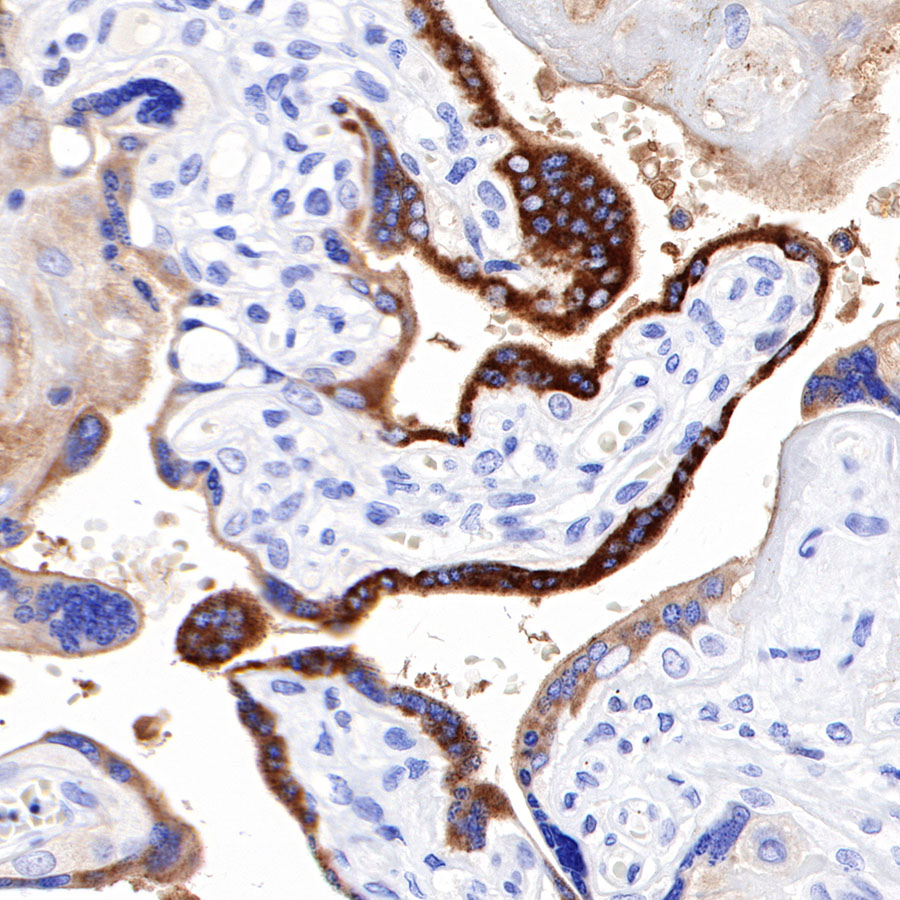

IHC shows positive staining in paraffin-embedded human placenta. Anti-PAPP-A antibody was used at 1/1000 dilution, followed by a HRP Polymer for Mouse & Rabbit IgG (ready to use). Counterstained with hematoxylin. Heat mediated antigen retrieval with Tris/EDTA buffer pH9.0 was performed before commencing with IHC staining protocol.